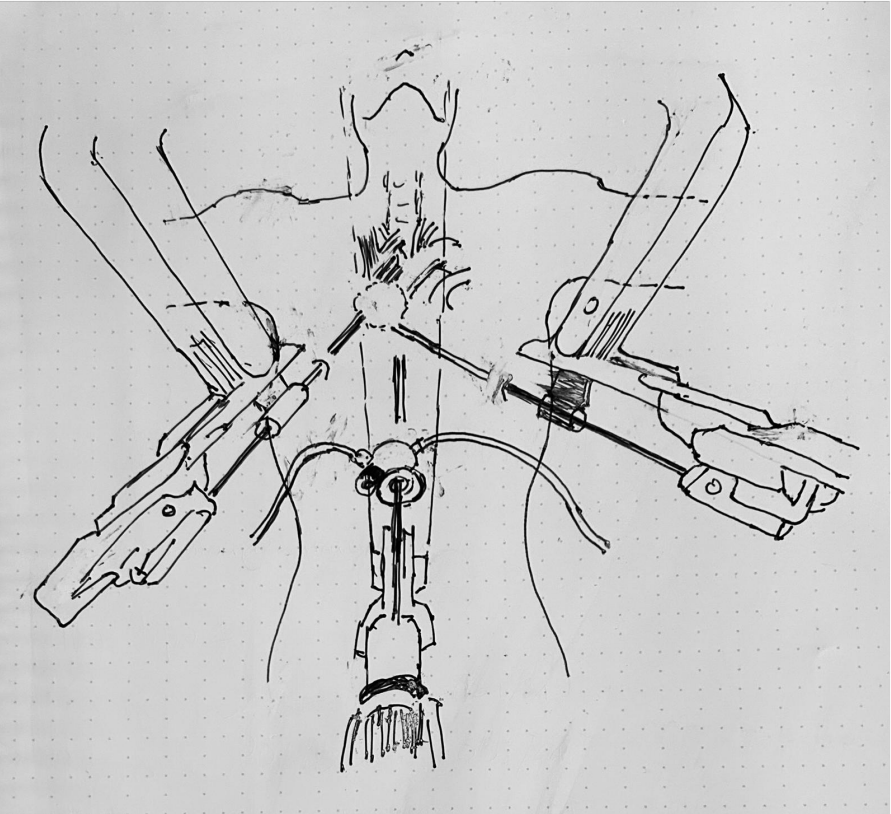

2: Graphic Representation of Port Placement and Patient Disposal

The surgeons performed a 3 cm subxiphoid incision. A GelPort (S) was placed, and CO2 was insufflated with pressure from 8 to 10mmHg. The camera port was introduced through the GelPort in the subxiphoid area. Under direct view, the surgeons introduced an operative port in the seventh right intercostal space on the anterior axillary line. Then, the second operative port was placed in the contralateral intercostal space, again at the level of the anterior axillary line. The docking required less than four minutes. A fenestrated bipolar forceps was introduced through the right port, and the bipolar Maryland was introduced in the left chest cavity.